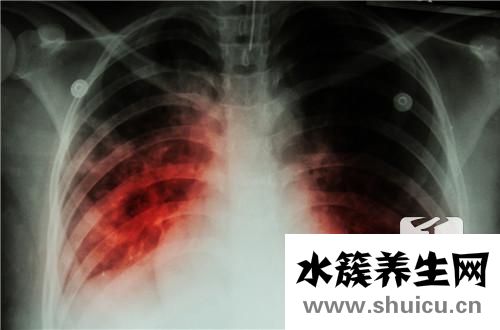

?結核病是一個普遍的問題,它將對人的身體造成很大的壓力,結核病的原因很多,通常與病理因素有關,許多人的肺功能本身是正常的,但是由于長期吸入這些非生態(tài) 細菌會產(chǎn)生巨大的肺泡,導致病毒吞噬,并逐漸導致...